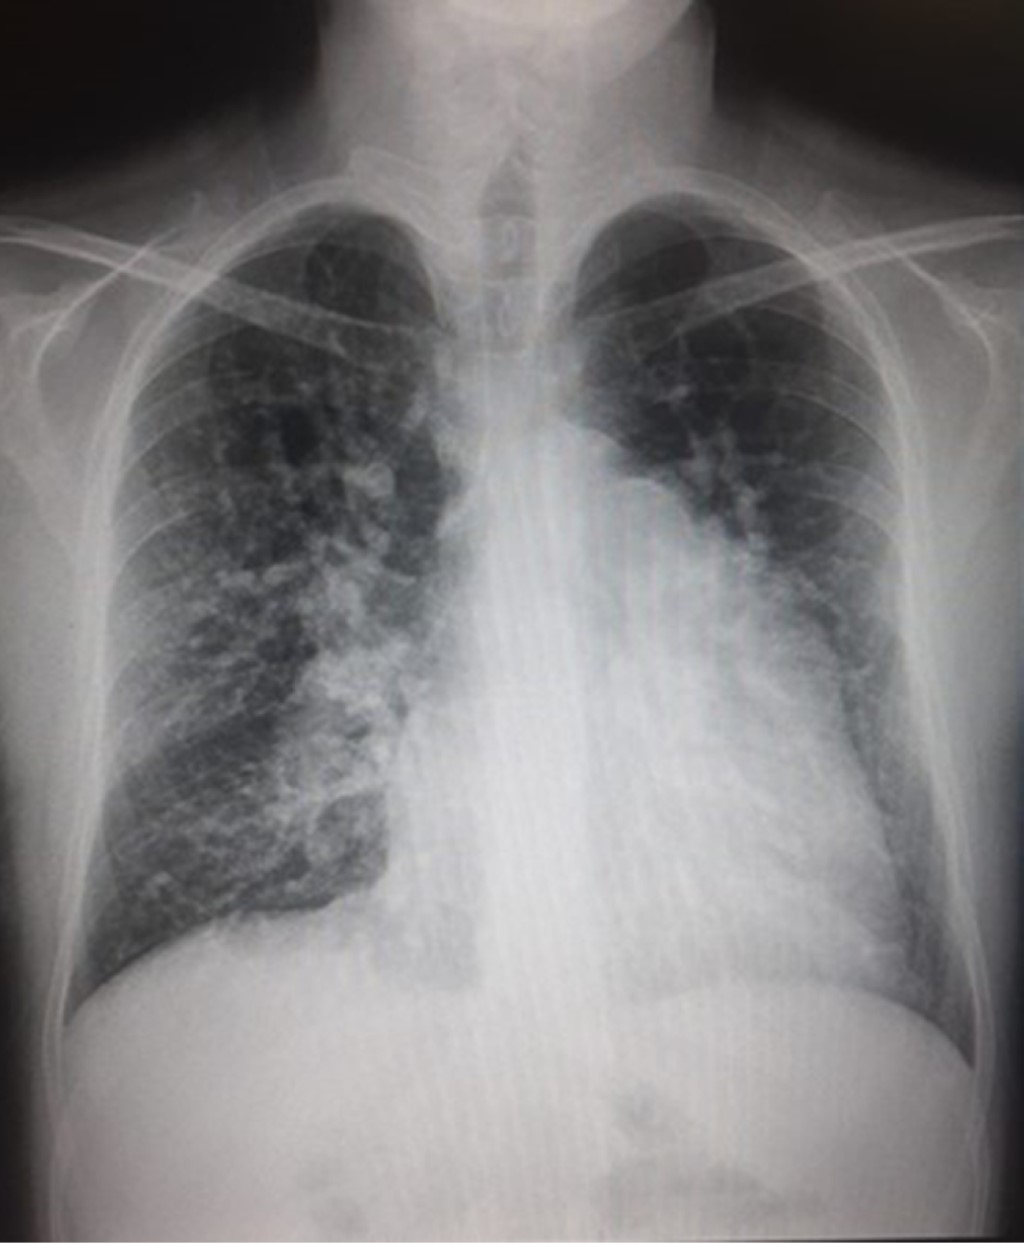

Ventrículo único en adulto de 28 años de edad, historia y actualidad de un corazón no quirúrgico

Herrera-Morales JA, Becerra-Gutiérrez CA, Cazares-Hernández KE, Palomares-Alonso VI

Introducción: el ventrículo único es una patología poco frecuente dentro de las cardiopatías congénitas en el adulto. Este es un grupo de anomalías graves de la estructura del corazón tras un mal desarrollo, que da como resultado una sola cámara ventricular. En esta población las medidas farmacológicas son poco eficaces para evitar la progresión de una falla cardiaca terminal; sin embargo, existen procedimientos quirúrgicos que ayudan a alargar la supervivencia y la calidad de vida. Objetivo: reportar el caso de una cardiopatía congénita en el adulto de baja prevalencia. Caso clínico: se presenta el caso de un hombre de 28 años con antecedente de cardiopatía congénita cianógena de tipo corazón univentricular de morfología indeterminada con doble vía de salida diagnosticada desde su primer año de vida, que ha llevado solamente manejo médico. Conclusiones: desafortunadamente, al ser una cardiopatía congénita poco frecuente en los adultos, existen pocas referencias sobre su manejo médico. Si no son sometidos a intervención quirúrgica en edades tempranas, lo que ofrece mayor calidad de vida y supervivencia, algunos pacientes fallecen durante la lactancia debido a insuficiencia cardiaca.

Figura 2